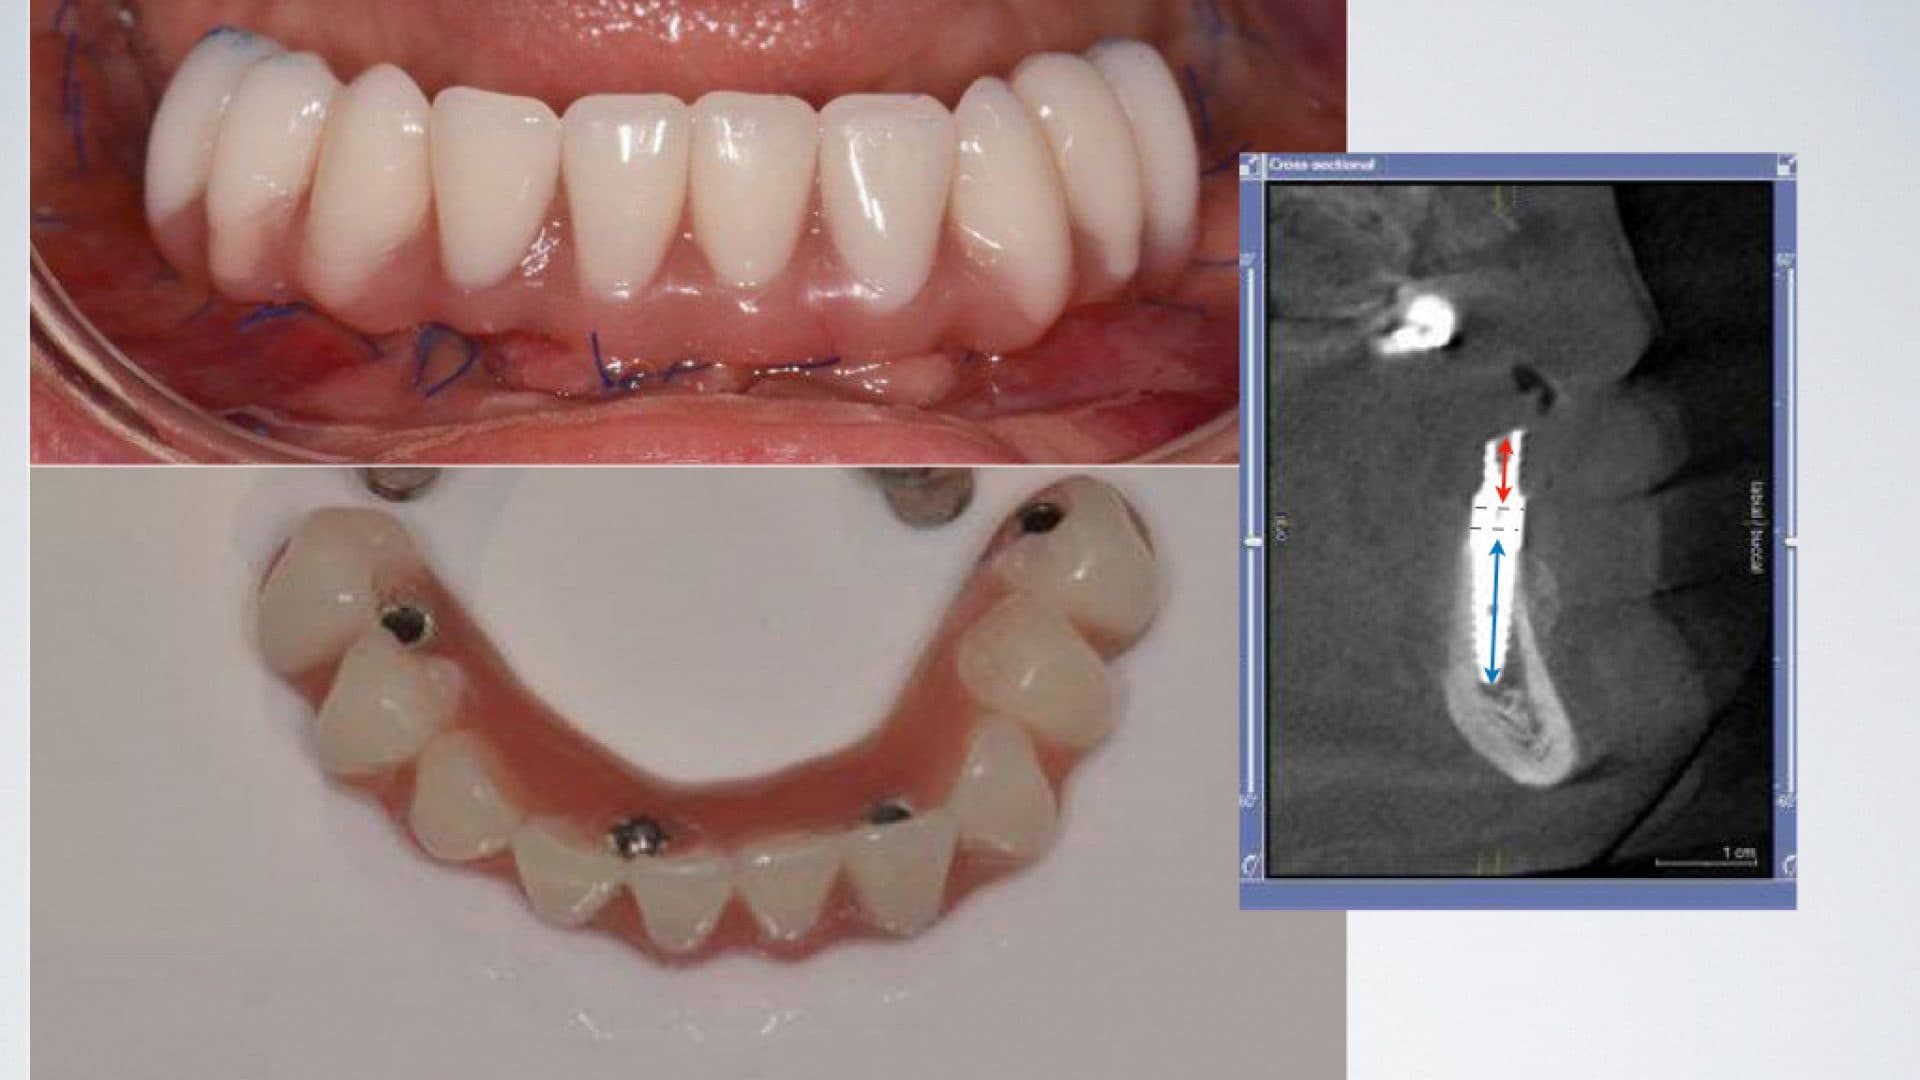

i. Even spread of the implants and flat and uniform under-surface/interface between the prosthesis and the natural gums. A deviation from this will affect the cleanability of the prosthesis, food entrapment and smell (See pictures);

Ideal Situation

ii. The access holes for the screws are located near the edges of the front teeth and in the middle of the back teeth. Any deviation from this will severly affect level of comfort, speech, and also cleanability (See pictures);